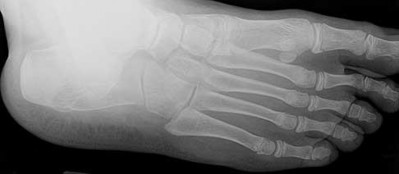

Figures 1a through 1c

Calcaneonavicular (CN) coalition

- Calcaneonavicular (CN) coalition**_

Tarsal coalitions occur when primitive mesenchymal cells fail to differentiate and form the

normal articular separations between the tarsal bones of the hindfoot. Overall incidence is difficult to determine because many affected people are minimally symptomatic or asymptomatic. Symptomatic tarsal coalitions typically present in adolescents as a painful flatfoot; however, there are a number of possible presentations, and occasionally symptoms do not appear until adulthood. Most tarsal coalitions are between the calcaneus and the navicular (CN) and the talus and the calcaneus (TC). Although most TC coalitions are across the middle facet, posterior facet coalitions do occur. Plain radiographic evaluation of suspected tarsal coalition is the mainstay for diagnosis. However, coalitions can be bony or fibrous, and making the diagnosis can be difficult. The addition of CT images to distinguish bony definition and MR images to decipher soft tissue can aid in diagnostics. Bony coalitions appear as definite bony bridging between the bones, while fibrous coalitions are suspected when distortion of the bony anatomy is seen. Bony coalitions are best seen on the oblique view (CN) and Harris axial view (TC). There are a number of secondary signs such as the anteater (AE) sign (elongation of the anterior process of the calcaneus as it extends to the navicular as seen on the lateral view [CN]). talar beaking (traction spur of the talar neck thought to result from abnormal stresses as seen on the lateral view [both CN and TN]), and the “C” sign (a continuous cortical contour from the medial talus to the sustentaculum tali [ST]) as seen on the lateral view (TC). A number of newer signs are not as well known, such as a broad mediolateral dimension of the navicular on the anteroposterior (AP) view (the

navicular is wider than the talar head [CN]), nonvisualization of the middle facet on the lateral view (TC), the brick sign (a normal ST is flat, but a distorted ST is enlarged and curved [CN]), and a tapered lateral navicular bone as seen on the AP view (the medial navicular [CN] is much thicker than the lateral navicular).

Figure 1a shows talar beaking (TB), an AE, and an open middle facet (MF). Figure 1b shows a wide navicular (WN), and Figure 1c shows an abnormal articulation between the calcaneus and the navicular, all consistent with a CN coalition.